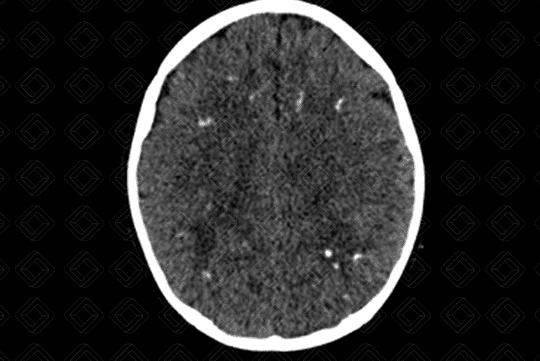

• Achados de imagem neurológicos: O rastreio inicia-se com ultrassonografia transfontanelar . Diante da gravidade das lesões e para avaliar a extensão das calcificações, pode ser realizada adicionalmente, tomografia computadorizada do crânio e até mesmo, ressonância magnética . Microcefalia e distúrbios de migração neuronal são achados pouco comuns. As calcificações costumam ser mais grosseiras e aleatórias no parênquima encefálico. Das infecções congênitas é a que mais comumente cursa com hidrocefalia (casos mais graves), disgenesia do corpo caloso e envolvimento cerebelar (figura).